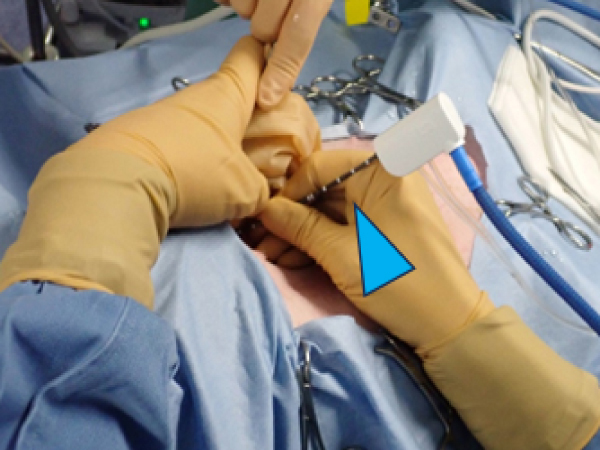

外側左葉に63.3㎜×61.5㎜の肝臓腫瘍が認められ細胞診にて肝細胞癌と診断されたました。 摘出も可能でしたが高齢であり、過去に何度か開腹手術もしており、甲状腺がんの摘出も同時に手術を行うため負担の少なさを考慮しフュージョンイメージングを用いてアブレーションを実施しました。 超音波ガイド下で肝臓腫瘍の周囲に生理食塩水を満たすことで周囲の組織を熱で損傷することなく安全に実施が可能です。 術後の経過も良好で次の日に退院しました。

アブレーション実施の様子

超音波を当てながらアンテナ(青矢頭)を挿入している